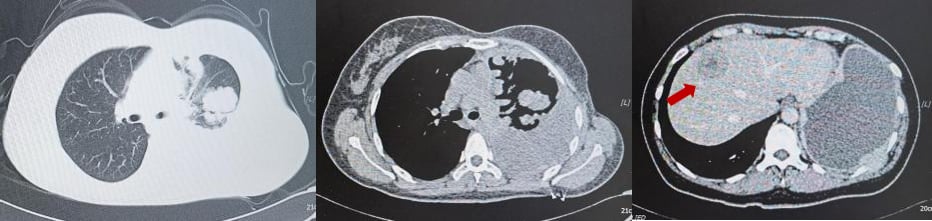

2023年11月,患者再次出现疾病进展,胸腹部CT显示肝内多发软组织肿物较前明显增多增大。肝穿刺活检病理再次确认转移性低分化腺癌,HER2(3+)阳性。

此时,患者入组了一项III期临床研究,比较FS-1502和T-DM1(恩美曲妥珠单抗)在HER2阳性不可手术切除的局部晚期或转移性乳腺癌患者中的疗效和安全性。她被随机分配到对照组,接受了14周期的恩美曲妥珠单抗治疗。恩美曲妥珠单抗是一种抗体-药物偶联物(ADC),它像一个“精准制导的化疗药”,通过抗体部分识别并结合癌细胞表面的HER2蛋白,然后将化疗药物精准地输送到癌细胞内部,减少对正常细胞的损伤。治疗后,患者肝功能异常I-II级,无骨髓抑制,疗效评价为部分缓解(PR)。临床试验不仅为患者提供了前沿治疗机会,也大大减轻了经济负担。